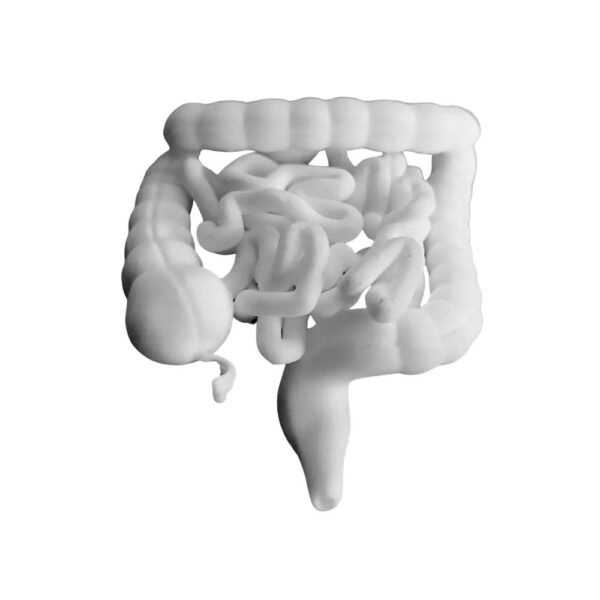

Visualisez l’anatomie digestive en 3D avec cette reproduction fidèle du système intestinal. Ce modèle didactique permet de distinguer clairement le côlon de l’intestin grêle, idéal pour l’enseignement ou la démonstration patient.

| Modèle du Tractus Intestinal : Gros Intestin et Intestin Grêle | 1 6500 د.ج |